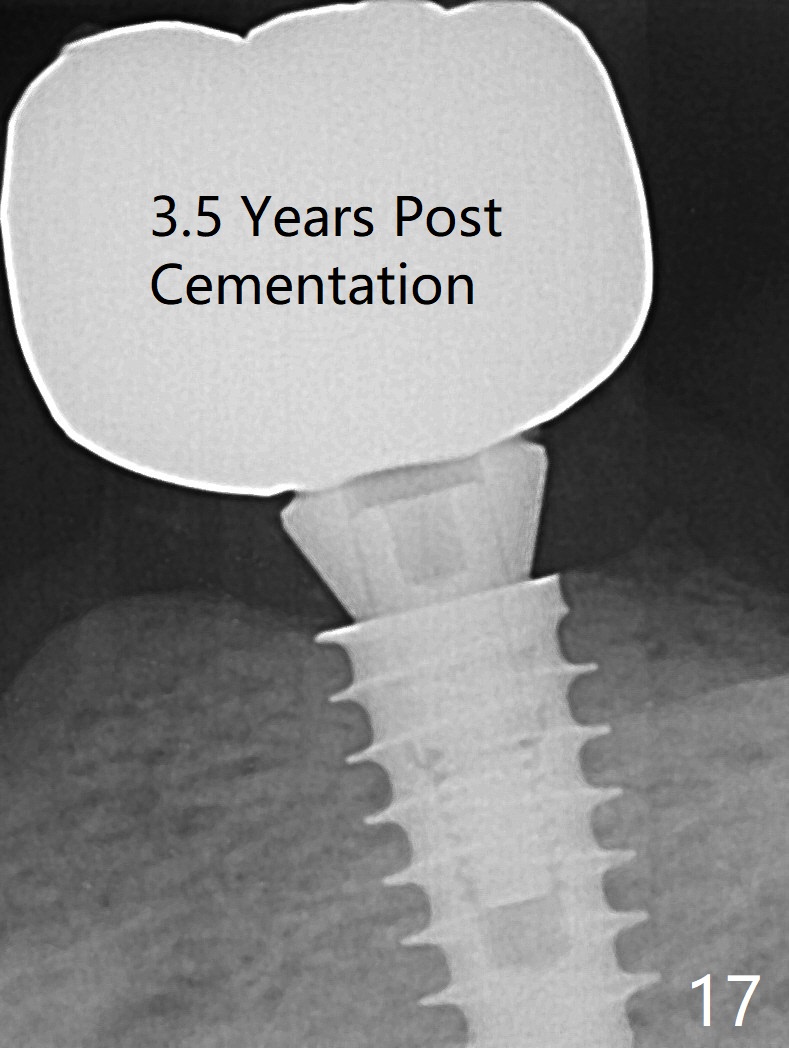

The implant osteointegrates 2 months postop (Fig.9). A pair abutment is placed (Fig.10: 5x4(2) mm) for a provisional (Fig.11). Wax up for final restorations (Fig.12-15). There is no bone resorption 1 year 4 months post cementation (Fig.16). The RPD is doing fine. The implant remains stable 3.5 years post cementation (in spite of open margin), while the other abutment for the RPD (the tooth #30) has mobility with gingival recession.